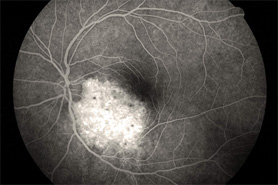

A Case of Subretinal Tumor (Choroidal Hemangioma)

ABOVE LESION CLEARLY DEMONSTRATED IN A FLUORESCEIN ANGIOGRAM